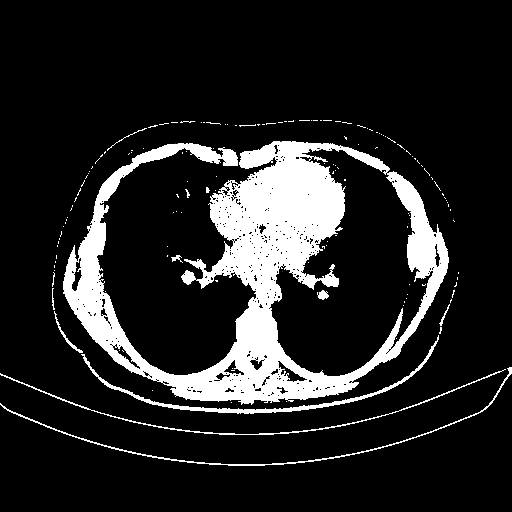

Original VENOUS CT scan

Full window (WL 1023.5, WW 4095 β†’ Low βˆ’1024, High +3071)

Actual HU range: [-1024.0, 3071.0]